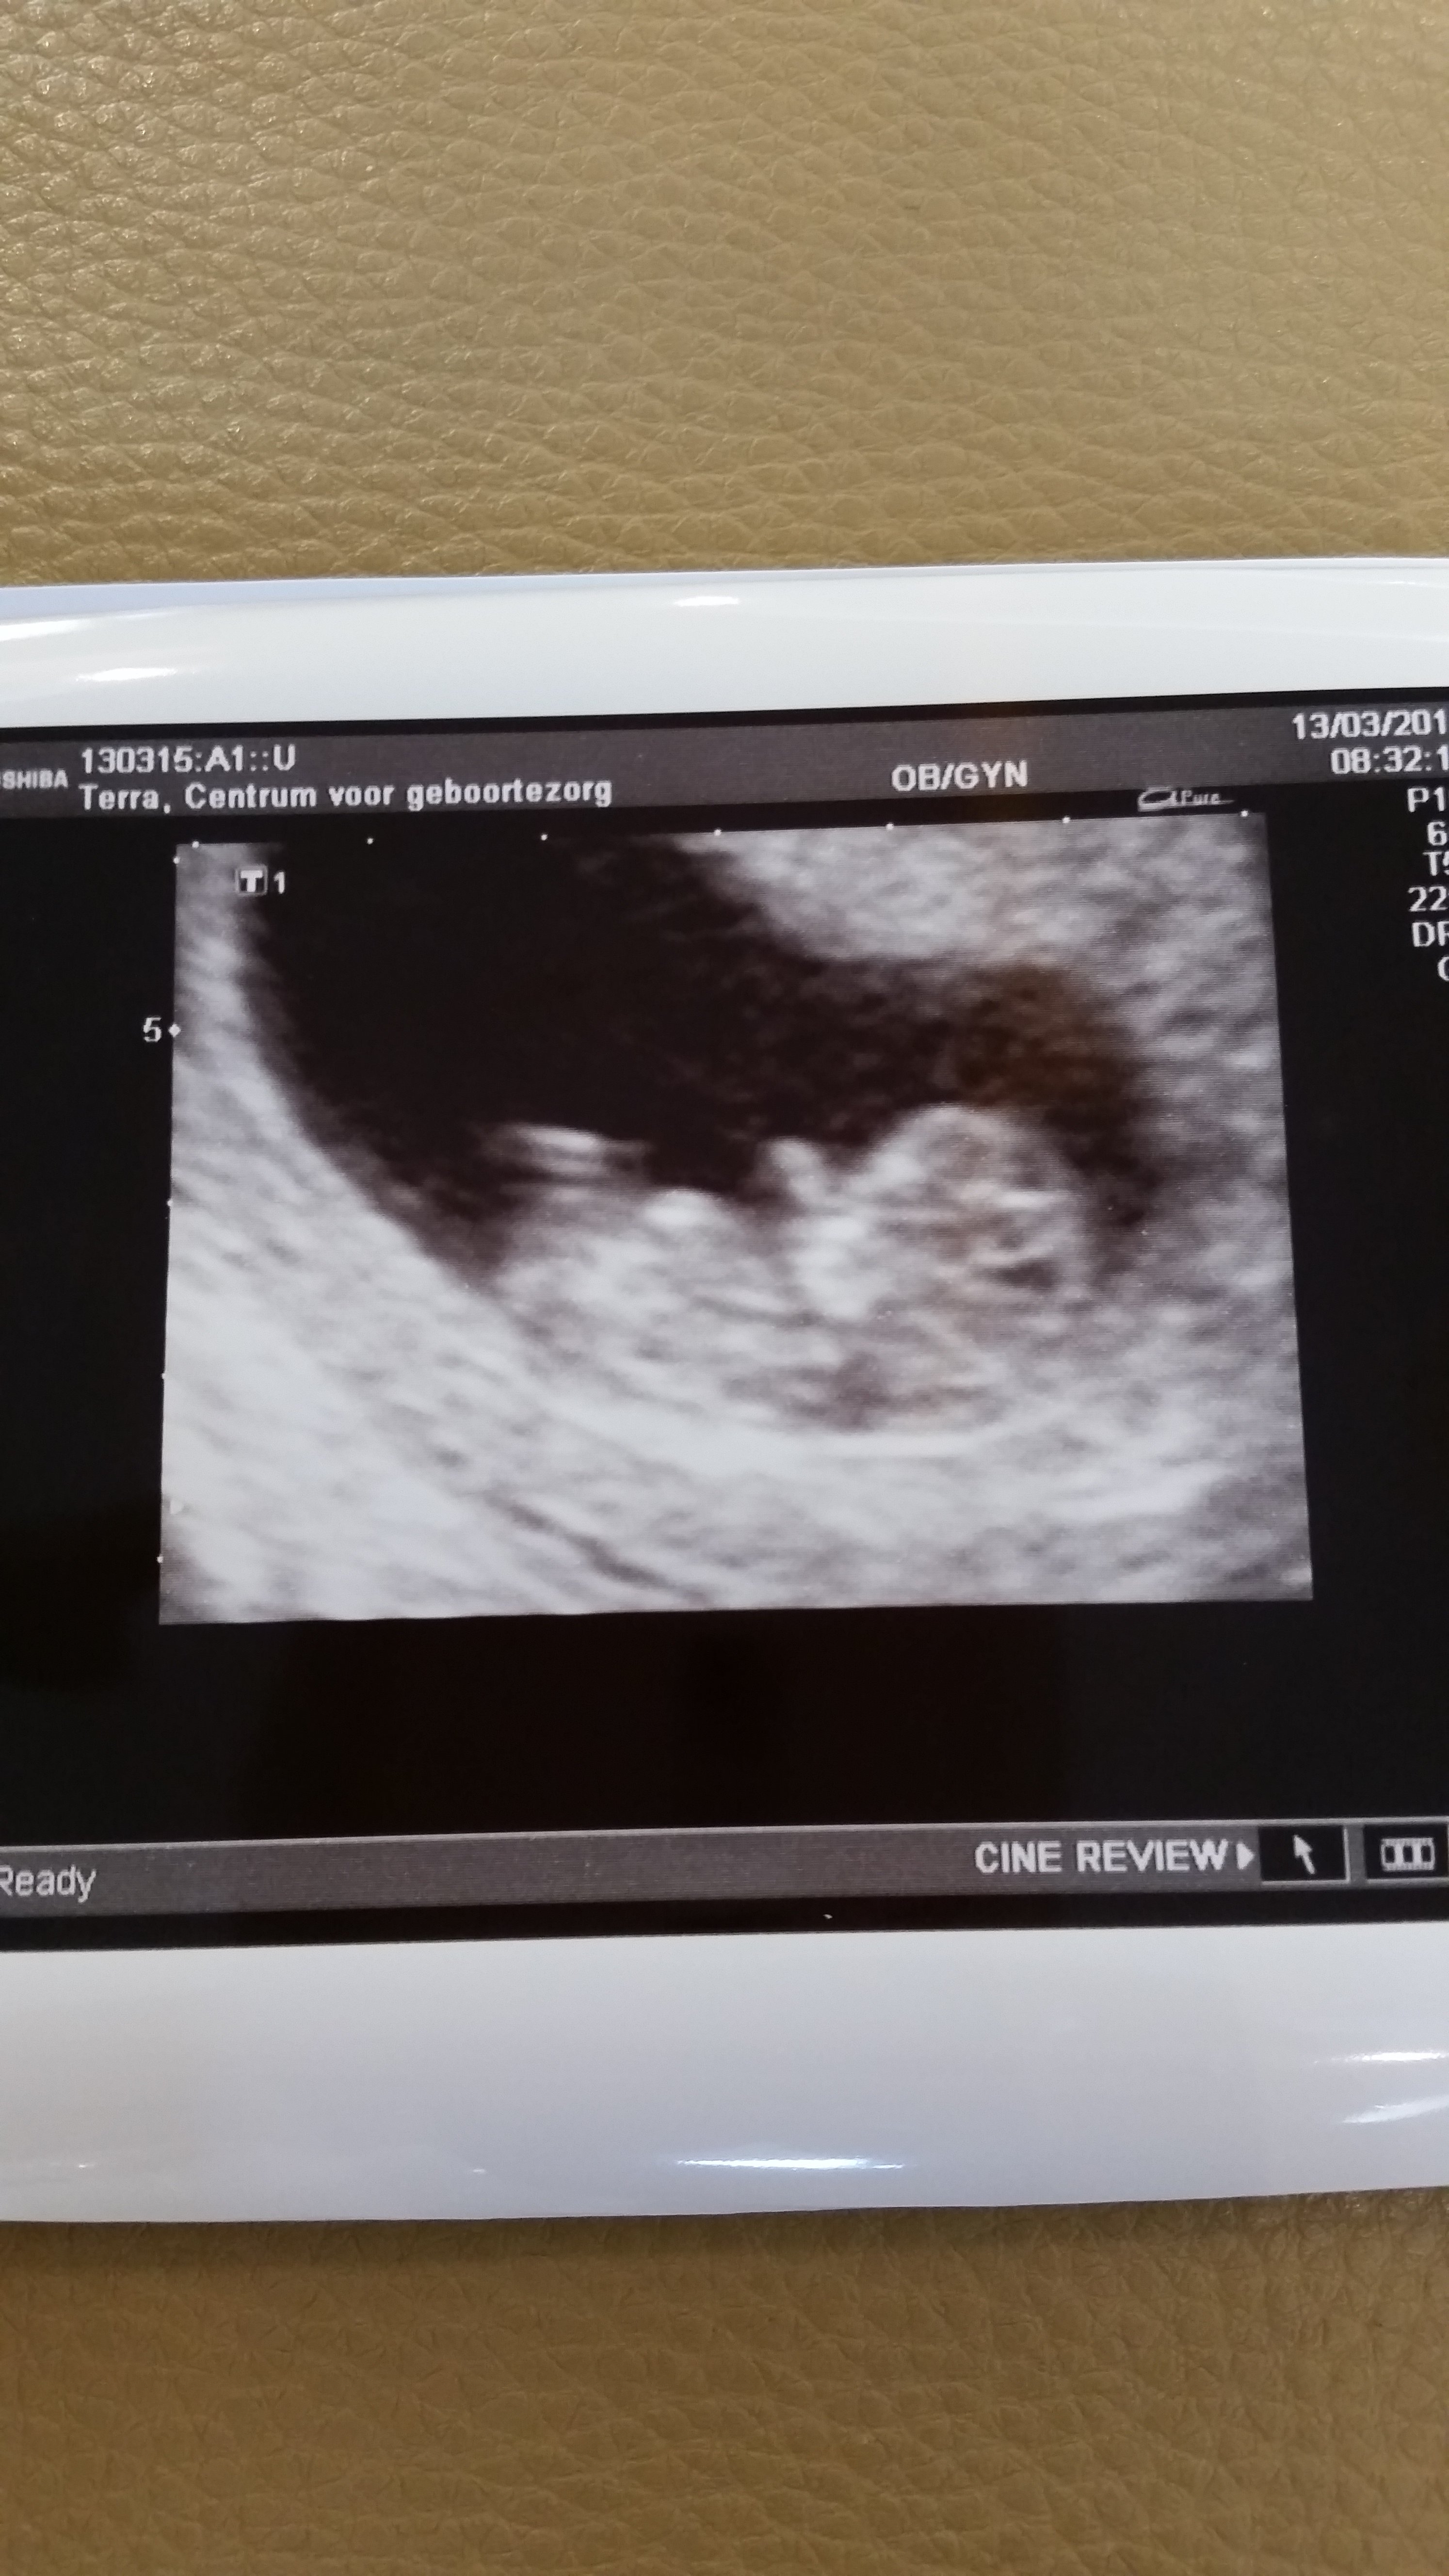

masalllahhh masalllahhh kuzucua allahımm kucaına almayıda nasip etsn insallah canm bizde görürüz insallah bebism bu kadar yok benim daaa kücüüz biz beklememiz lazımm allahıımmm herkese yasatsınn bu duyguları insallah aminnTeyzeleri 11 haftalik 2. Ultrasyona gittik🙂 masallah suphanallah zib zib durmadi yerinde kucuk haliyle.. 3,5 cm suan🙂 Rabbim sizlerede yasattsin bu mutlulugu en tez vakitte canlarmEkli dosyayı görüntüle 49792

oyyyy maşallah allahım görünce kalbim nasıl küt küt attı kim bilir kendiminkini görünce kalbim dayanmaz herhalde 🙂Teyzeleri 11 haftalik 2. Ultrasyona gittik🙂 masallah suphanallah zib zib durmadi yerinde kucuk haliyle.. 3,5 cm suan🙂 Rabbim sizlerede yasattsin bu mutlulugu en tez vakitte canlarmEkli dosyayı görüntüle 49792